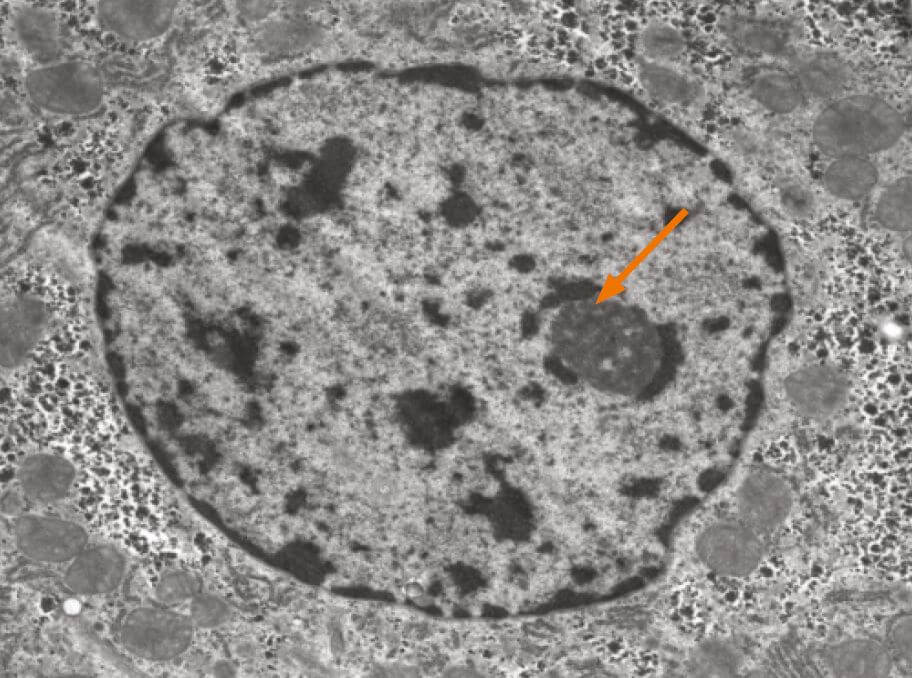

The nucleolus is the most prominent structure in a cell nucleus. It is the site of ribosomal RNA (rRNA) transcription, pre-rRNA processing and ribosome subunit assembly. The nucleolus is a dynamic structure that assembles around the clusters of rRNA gene repeats during late telophase, persists throughout interphase and then disassembles as cells enter mitosis. Alterations in both number and shape of nucleoli are linked to cancer and cancer prognosis.

The nucleolus is a ribosome factory, composed of deoxyribonucleic acid (DNA), ribonucleic acid (RNA), and protein. At the nucleolus, a long ribosomal RNA (rRNA) precursor molecule is transcribed from DNA, processed into three mature RNAs, and packaged together with specific proteins to make the large and small ribosomal subunits. Once the subunits have been assembled, they are transported out of the nucleolus to the cytoplasm for use in translation (protein synthesis). Human chromosomes contain five nucleolar organiser regions (called NORs), located on the short arms of the chromosomes 13, 14, 15, 21, and 22. In humans, each NOR contains approximately one hundred tandemly repeated rRNA gene copies. The NORs of different chromosomes typically come together in interphase. Thus, a single nucleolus is often made up of rRNA genes from two or more different NORs.

Internuclear structures do not have membranes, but the density of nucleoli makes them quite visible with most nuclear staining’s. It is, however, a challenge to obtain a proper segmentation of nuclei in light microscopical images, a requirement for quantitative measures.